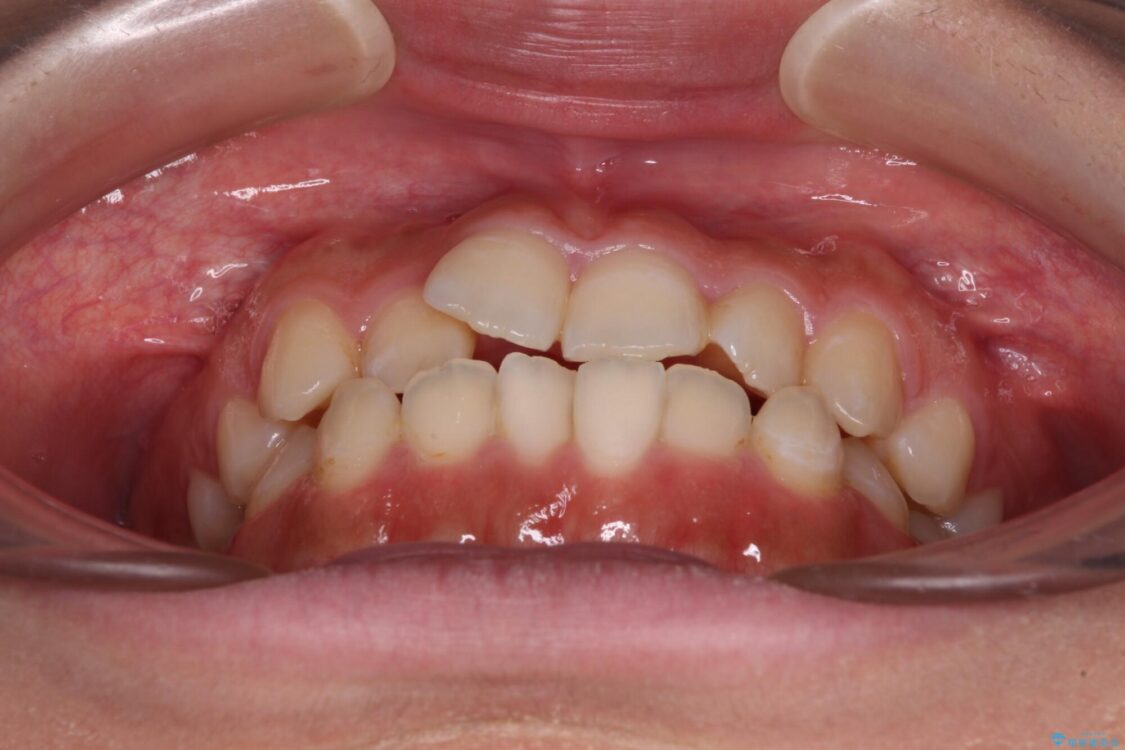

前歯のデコボコを気にして来院された患者様です。

治療前

• 【モニター】短期間で終わりたい ワイヤー装置での非抜歯矯正 治療前画像